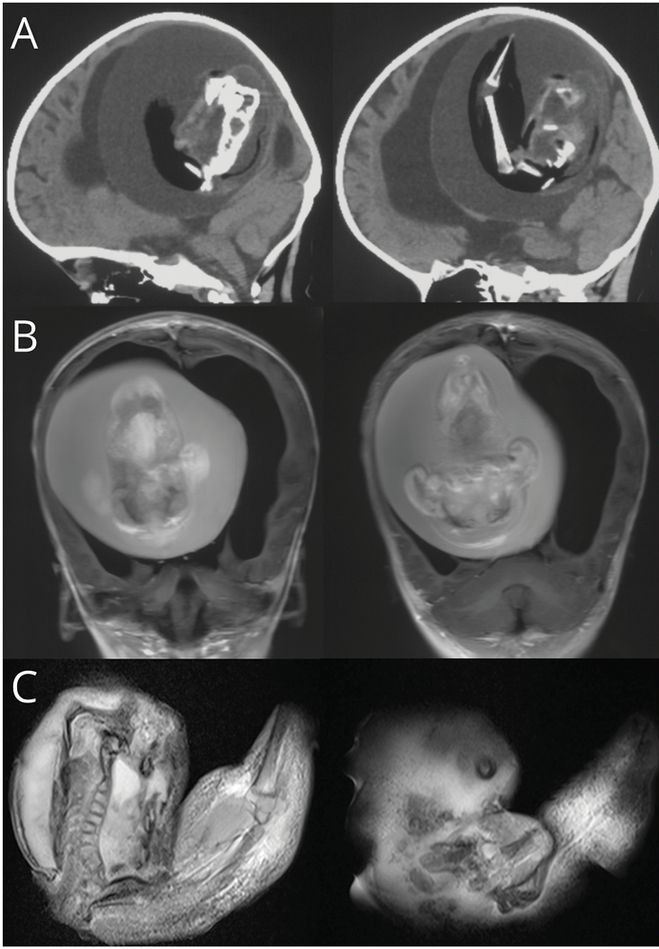

Mulher de 81 anos morreu depois de descobrir que carregava um bebé calcificado. Feto já lá estava há 56 anos

Daniela já andava a ser tratada no seu centro de saúde por causa de uma infeção urinária, mas as dores tornaram-se tão fortes que teve de dar entrada no hospital. Depois de descobrirem o feto, a mulher foi submetida a uma cirurgia.